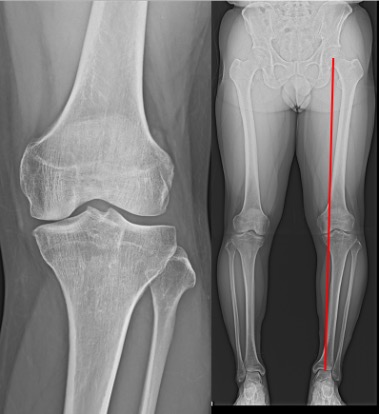

高位脛骨骨切り術(high tibial osteotomy: HTO)

初期の変形性膝関節症や大腿骨顆骨壊死などに適応があります。

O脚変形のために内側に偏った荷重線を、自分の骨を骨折させ角度を変えることにより、比較的きれいな軟骨の存在する外側に荷重線を移動させる手術です。荷重線が移動することによって膝の痛みが緩和されます。